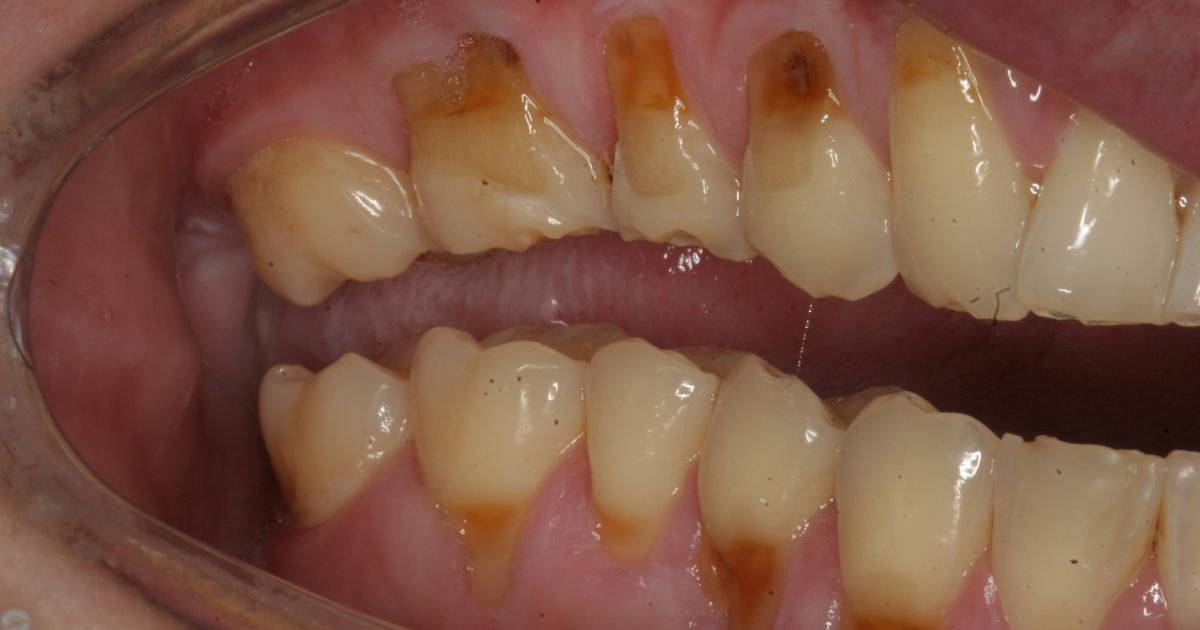

Damaged Teeth

A number of studies have concluded periodontal disease, which refers to inflammatory conditions that affect various structures in the mouth (including the gums), increases an individual's risk of developing oral cancer. Periodontal disease also relates to gingivitis, where the gums swell, become painful, and may bleed; and periodontitis, where the gums can start to pull away from the teeth and cause other serious issues in the mouth. Loose teeth may also be its own independent risk factor, as mouth cancer causes chronic trauma to the oral mucosa. When biting down, some patients notice their teeth do not fit together as they once did. This can be due to a tumor on the jawbone, causing teeth to shift.